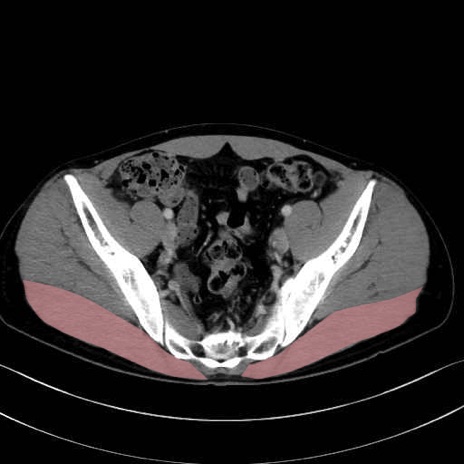

大殿筋 (Gluteus maximus)